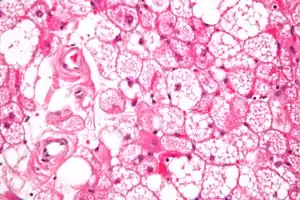

| Micrograph of a hibernoma. H&E stain. | |

The tumors histologically resemble brown fat. There are four histologic types recognized, but one is the most frequently seen (typical). There is a background of rich vascularity.

- Lobular type: Variable degrees of differentiation of uniform, round to oval cells with granular eosinophilic cells with prominent borders, alternating with coarsely multivacuolated fat cells (pale cells). There are usually small centrally placed nuclei without pleomorphism. The cells have large cytoplasmic lipid droplets interspersed throughout.[3][4]

- Myxoid variant: Loose, basophilic matrix, with thick fibrous septa, and foamy histiocytes

- Lipoma-like variant: Univacuolated lipocytes, with only isolated hibernoma cells

- Spindle cell variant: Spindle cell lipoma combined with hibernoma